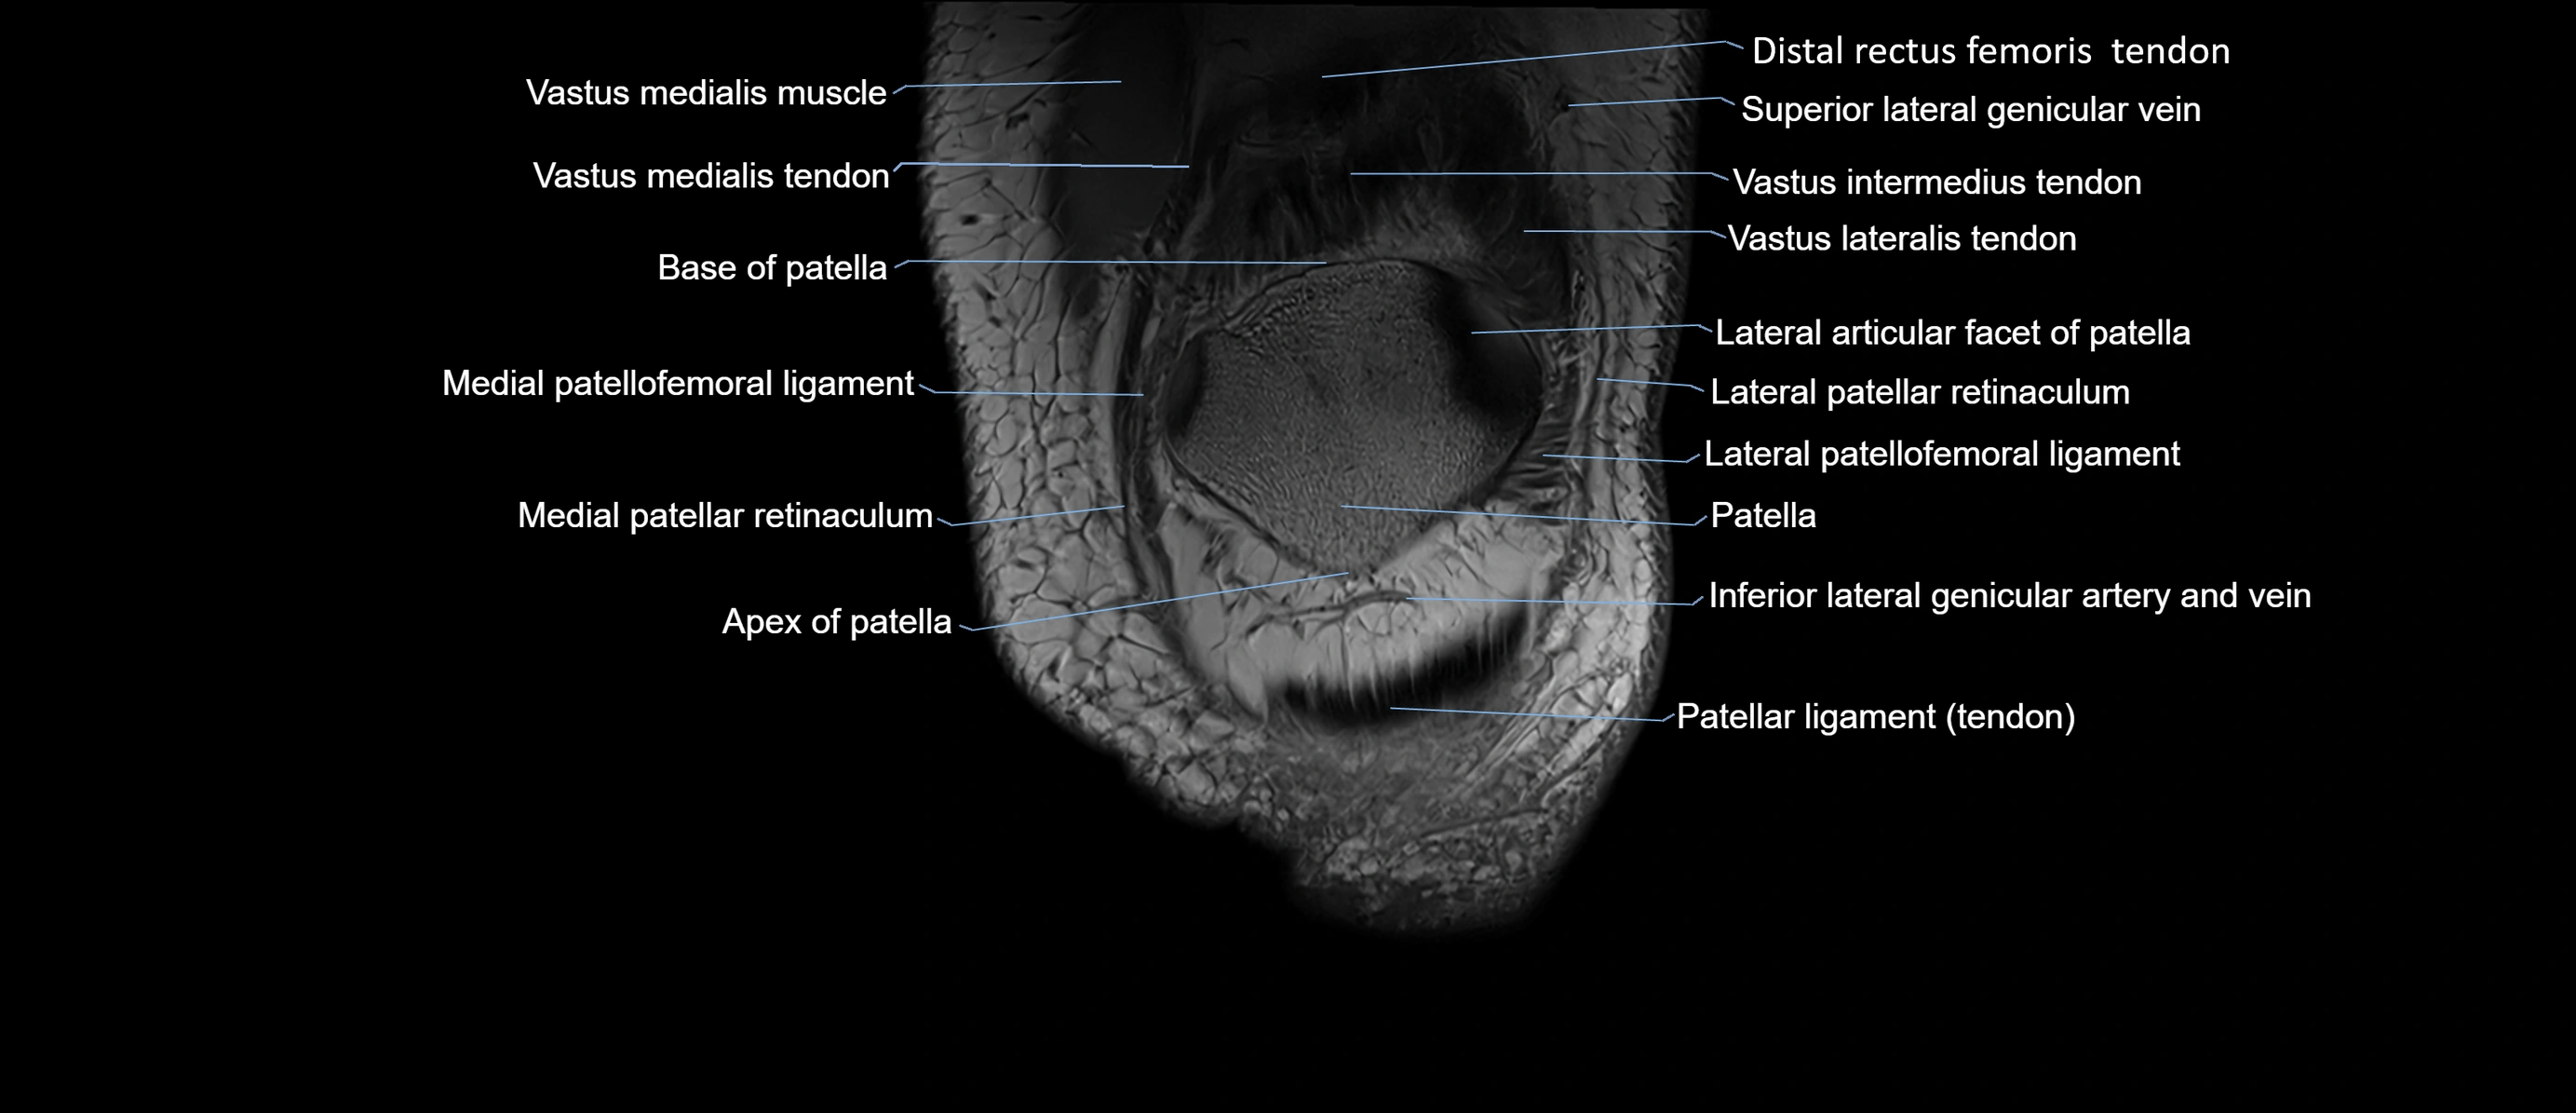

- Knee Joint